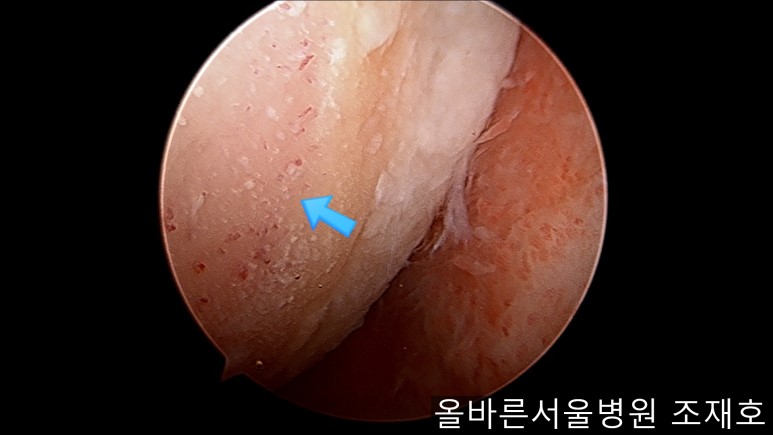

以注射的方式将CARTISTEM填满每一个孔。

填充完每个孔后将剩余的CARTISTEM涂抹在孔上方。